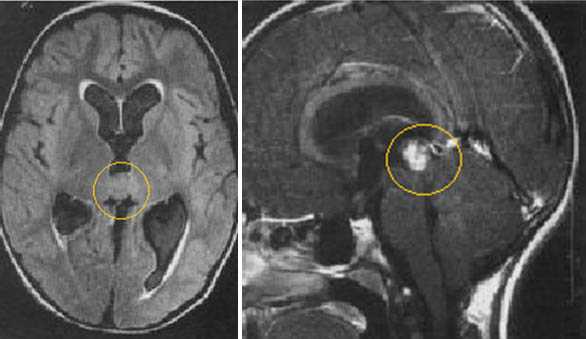

Диагностика: МРТ с контрастным усилением — стандартное исследование при опухолях этой локализации. При пинеоцитоме обнаруживают небольших размеров округлое образование в пинеальной области, с чёткими границами, активно и гомогенно накапливающее контраст и вызывающее компрессию пластинки четверохолмия. Для пинеобластомы характерны все признаки злокачественной быстро прогрессирующей опухоли (инфильтративный характер роста, гетерогенный сигнал с признаками некроза и кровоизлияний, большие размеры, субарахноидальные метастазы).

Пинеоцитома. МРТ в режиме Т2 и Т1 выявляется солидного строения опухоль задних отделов III желудочка мозга. На фоне в/в контрастирования определяется выраженный и достаточно гомогенный характер контрастирования опухоли.